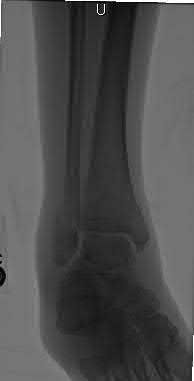

Figures A to C show radiographs of a 70 year-old male who fell on the ice 5 days ago. He could initially walk after the fall, but he is now unable to weight-bear on the leg due to pain. Physical examination shows diffuse ankle swelling, with no medial sided ankle tenderness. He is neurovascularly intact. The patient does not smoke and has no medical history. A gravity stress radiograph is demonstrated in Figure

D. After closed reduction, there is 2 mm of fracture displacement, no talar shift and the talocrural angle = 83 degrees. What is the most appropriate treatment?

Figure B demonstrates a mortise radiograph of a Weber B fibula fracture with a congruent mortise.